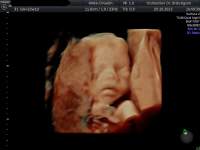

d.h. pränataler Ultraschall (Messung der Nackendicke, Organscreening) einerseits, andererseits kann noch eine Untersuchung mittels 4D-Ultraschall durchgeführt werden,

wo ein dreidimensionales Bild von Ihrem Kind angefertigt werden kann.

Dieses ermöglicht die Diagnostik einiger Fehlbildungen wie etwa der Lippen-Kiefer-Gaumenspalte, andererseits kann so das erste "Foto" von Ihrem noch ungeborenen Kind gemacht werden, was die Mutter-Kind-Beziehung zusätzlich fördert.